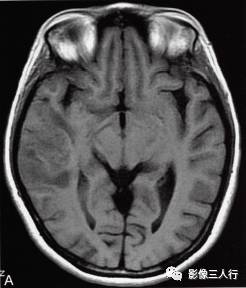

图1右颞叶横纹肌样脑膜瘤

A.T1WI横断面;B、C.T2WI横断面;D、E、F、G.增强横断面、矢状面、冠状面;H.HE×100

图1A:MRI T1WI示,右侧颞叶不规则形肿块,信号欠均匀,为稍低信号与小斑片状稍高信号混杂。其累及颞叶灰白质,界限欠清、边缘不整,大小约4.1cm×4.3cm×5.1cm。邻近脑沟脑裂变浅变平,周边脑实质受压。图1B、C:T2WI示,右颞不规则形肿块,信号欠均匀,为稍高信号与小斑片状略低信号混杂。灶周见带状高信号脑水肿。图1D~G:T1WI C示,右侧颞叶肿块呈不均匀的多个结节块状明显强化,邻近脑膜为线条状强化、增厚。